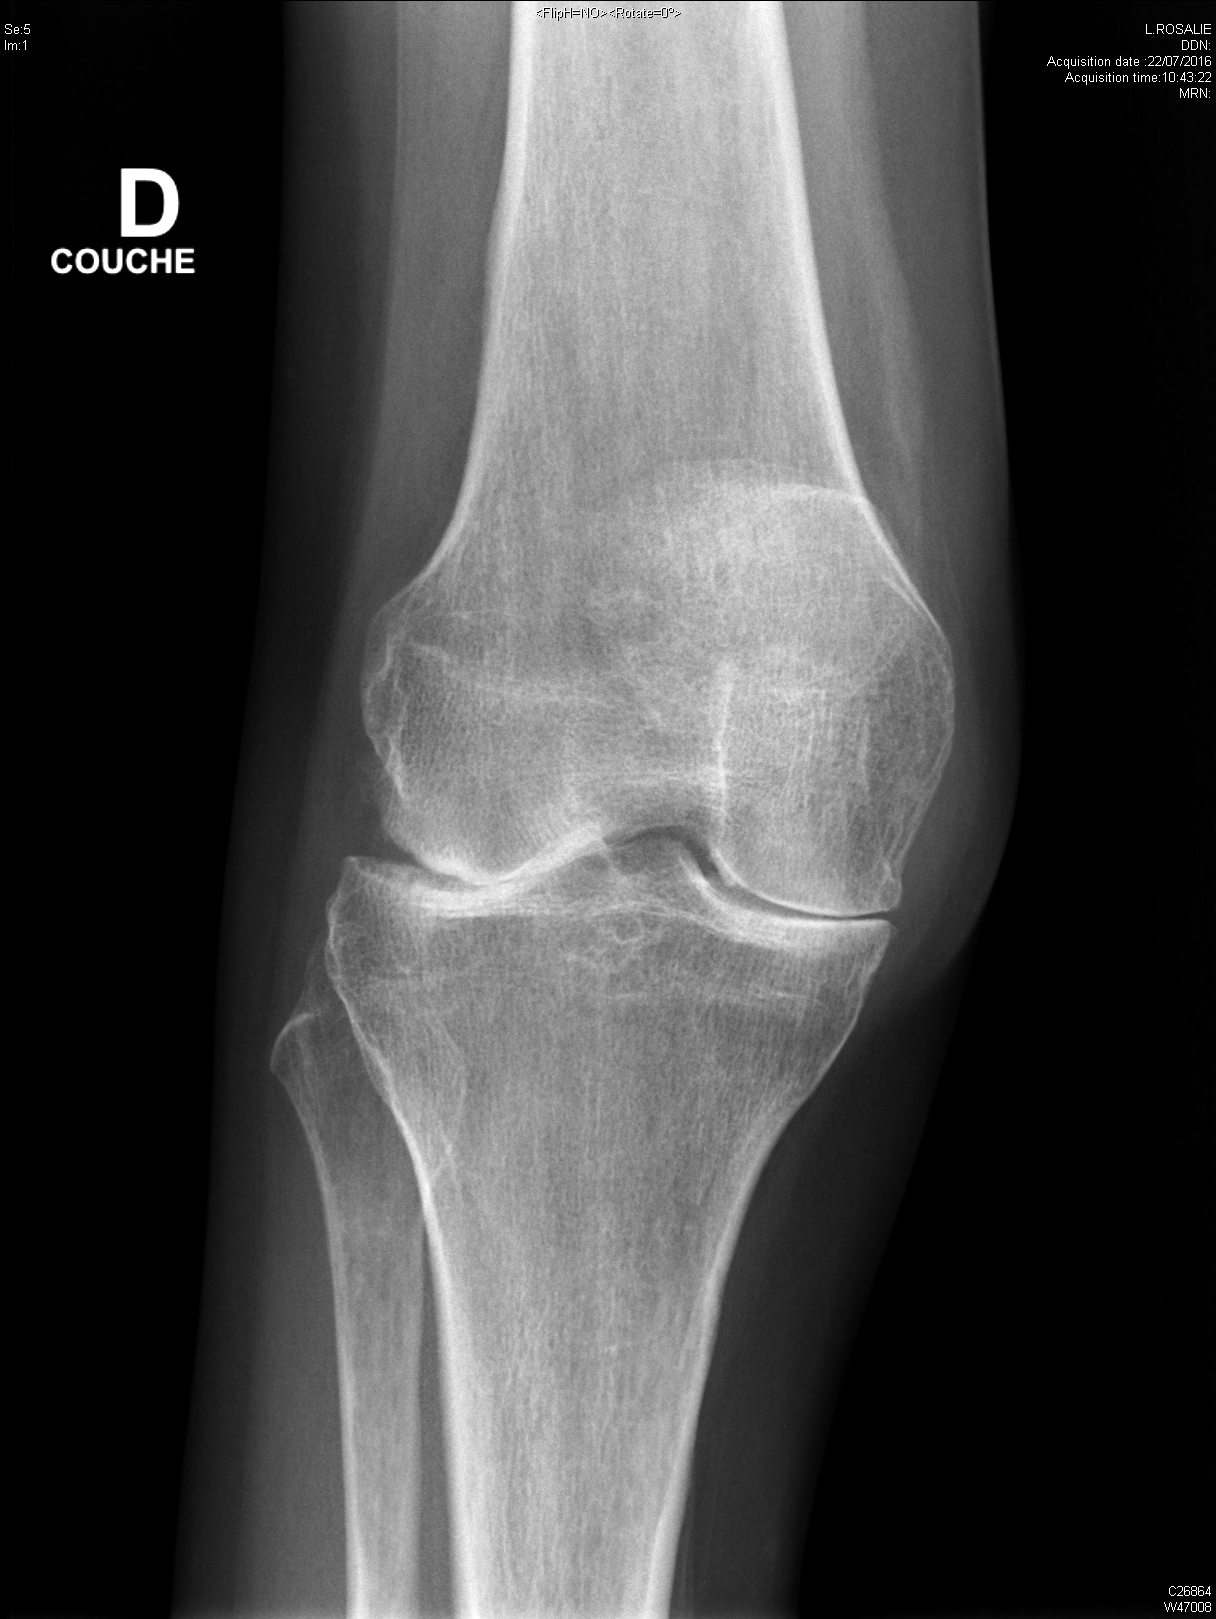

arthrite destructrice évoluée du genou dans le cadre d'une polyarthrite rhumatoïde